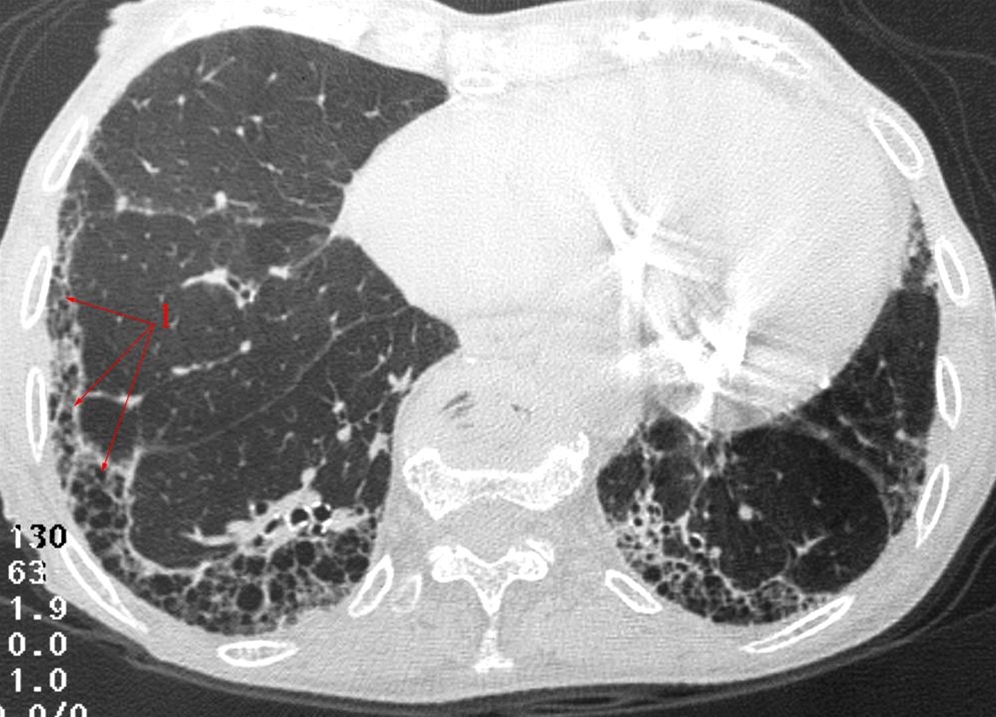

Lungefibrose, HRCT

HRCT (high resolution CT).

Tyndt CT-snit med stribeformede fortætninger, overvejende subpleuralt i periferien af begge underlapperne (1), såkaldt "bikubemønster", som ses ved lungefibrose.